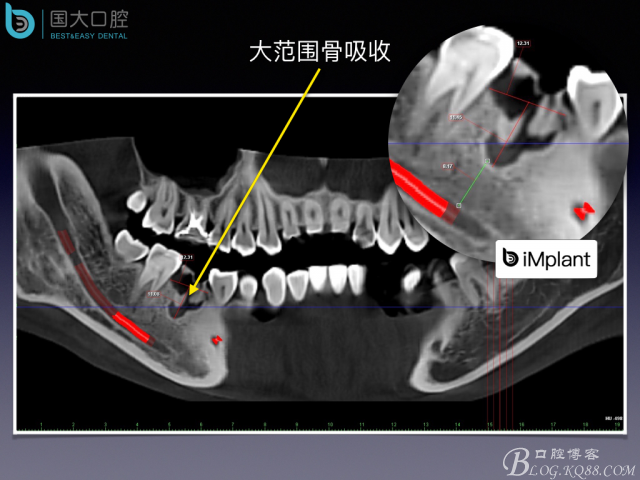

TypeC Socket即刻種植臨床案例

來源于國大口腔 邵現(xiàn)紅醫(yī)生發(fā)表的博文